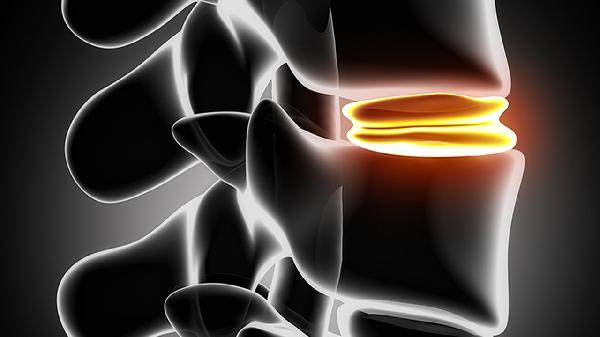

4、维持体态

长期驼背或脊柱侧弯会压缩椎间隙影响身高表现。坐立时保持耳朵与肩膀在同一直线,使用符合人体工学的桌椅。可每日练习靠墙站立5分钟,或进行瑜伽猫牛式等脊柱伸展动作。